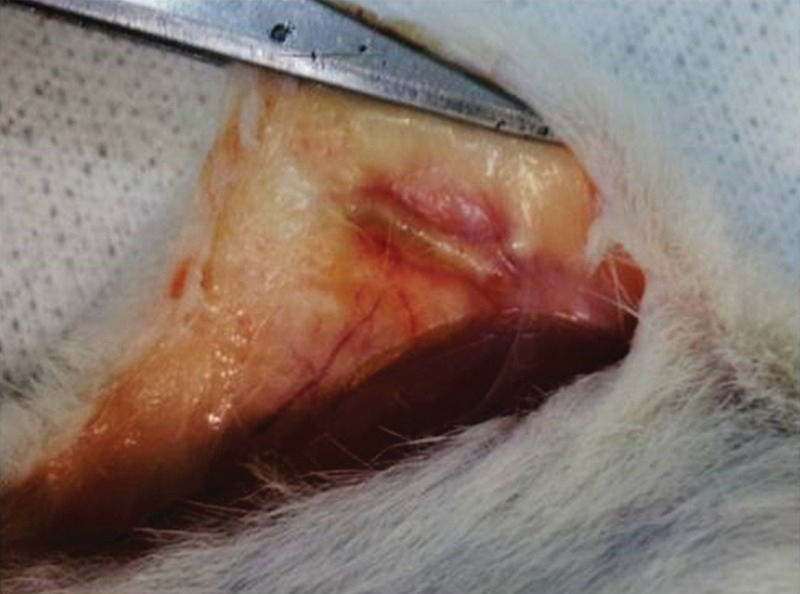

Figure 3 depicts the femur after 15 days of subcutaneous storage. The femur was swollen and fully covered by an inflammatory pseudocapsule. Both the diaphysis and epiphyses were widened. Handling of the graft confirmed that it had become more flexible because of fluid infiltration. Neither macroscopic bone nor bone marrow necrosis was prominent.

Syngeneic femur 15 days after implantation in the abdominal pocket.In the surgical picture, the subcutaneous tissue where the bone was positioned is swollen and hyperemic, and dilated blood vessels can be identified nearby. The bone is also mildly swollen and is fully encased by adherent inflammatory tissue (pseudocapsule). This foreign body-like reaction included multiple blood capillaries.